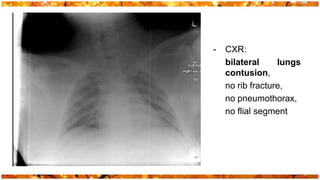

-   CXR:

bilateral     lungs

contusion,

no rib fracture,

no pneumothorax,

no flial segment

- CXR: bilateral lungs contusion, no rib fracture, no pneumothorax, no flial segment